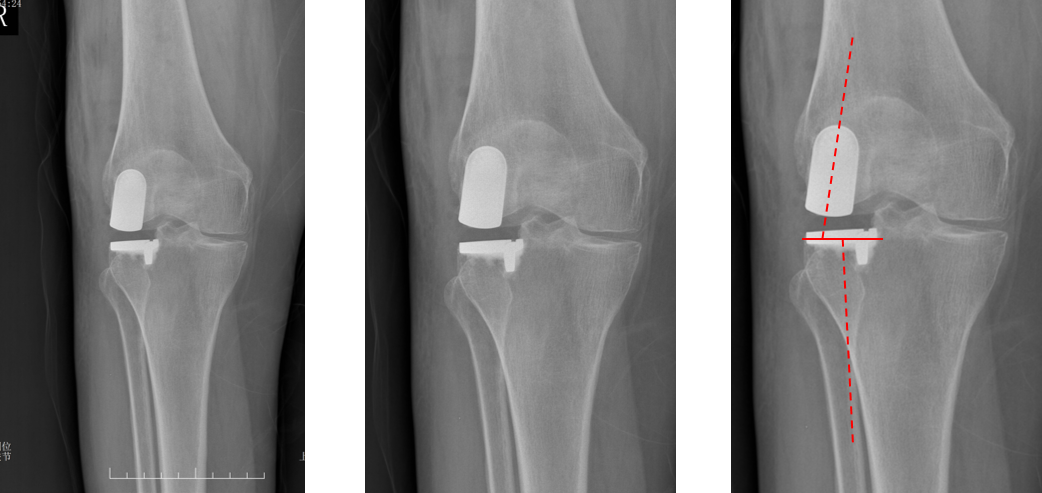

正位片标准胫骨和股骨假体位置

AP位假体位置:胫骨假体无明显内外翻,与胫骨轴线垂直,内侧缘与胫骨平台内侧缘齐平; 股骨假体长轴与胫骨假体垂直,中线一致。

侧位片标准胫骨和股骨假体位置

侧位片假体位置:股骨假体长栓与短栓平行,后倾35°;假体后缘与股骨后髁齐平,胫骨假体后倾7°,与胫骨平台前后缘齐平。

胫骨假体3°内翻

AP位胫骨与股骨假体位置:胫骨假体内翻3°,股骨假体中轴线与胫骨假体垂直。

胫骨假体厚度合适

胫骨垫片厚度合适:术前内翻畸形基本矫正,残留2-3°内翻。

胫骨假体内侧悬挂

AP位胫骨假体位置:胫骨假体内侧悬挂>2mm。

股骨假体偏内放置

AP位胫骨与股骨假体位置:股骨假体轻度内翻,中轴线与胫骨假体中线不一致,偏内侧。

胫骨假体偏大,且后倾不足

侧位胫骨假体位置:胫骨假体后侧悬挂>2mm,后倾2°。

胫骨假体后倾角度大

侧位片胫骨假体位置:胫骨假体后倾12°,前后缘齐平 。

股骨假体偏小

侧位片股骨假体位置:股骨假体偏小,与胫骨假体后缘不齐平;屈曲15°,未包容股骨后髁。

股骨假体偏大

侧位片股骨假体位置:股骨假体与胫骨假体不匹配,股骨假体大一个型号,屈曲45°,后缘空虚。

股骨假体屈曲角度大

侧位片股骨假体位置:股骨假体与胫骨假体匹配,股骨假体屈曲62°,前缘翘起。